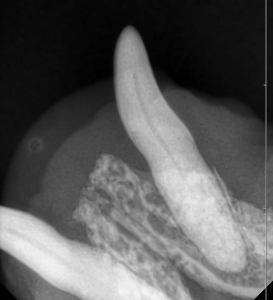

破折後の時間経過も長く、歯科レントゲンでは根尖病変を認めたため、抜歯をお勧めしました。

この子は、歯の状況を加味して抜歯しました。